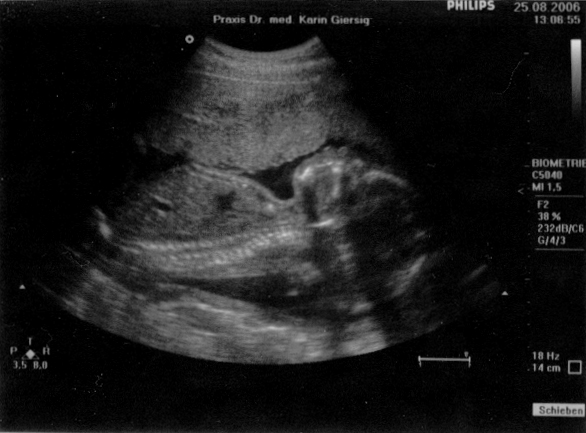

Ultraschall vom 26. Juni 2006

Scheitel-Steiß-Größe: 6,5 cm

Gesundheitszustand: einwandfrei

Geschlecht: unklar